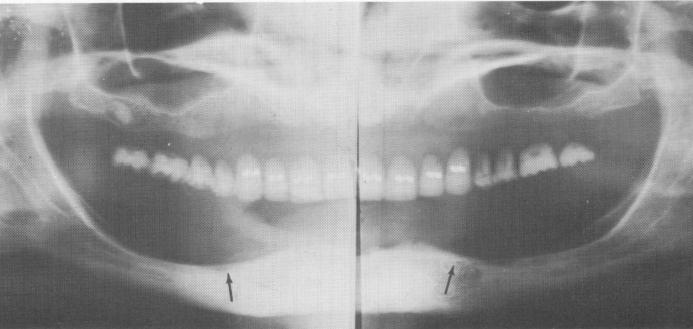

Fig. 12-17. Two Panorex x-rays of two different patients showing a unilateral dehiscency of the mental foramina on the right and left sides, respectively.

1 Panorex x-rays showing unilateral dehiscency of mental foramina